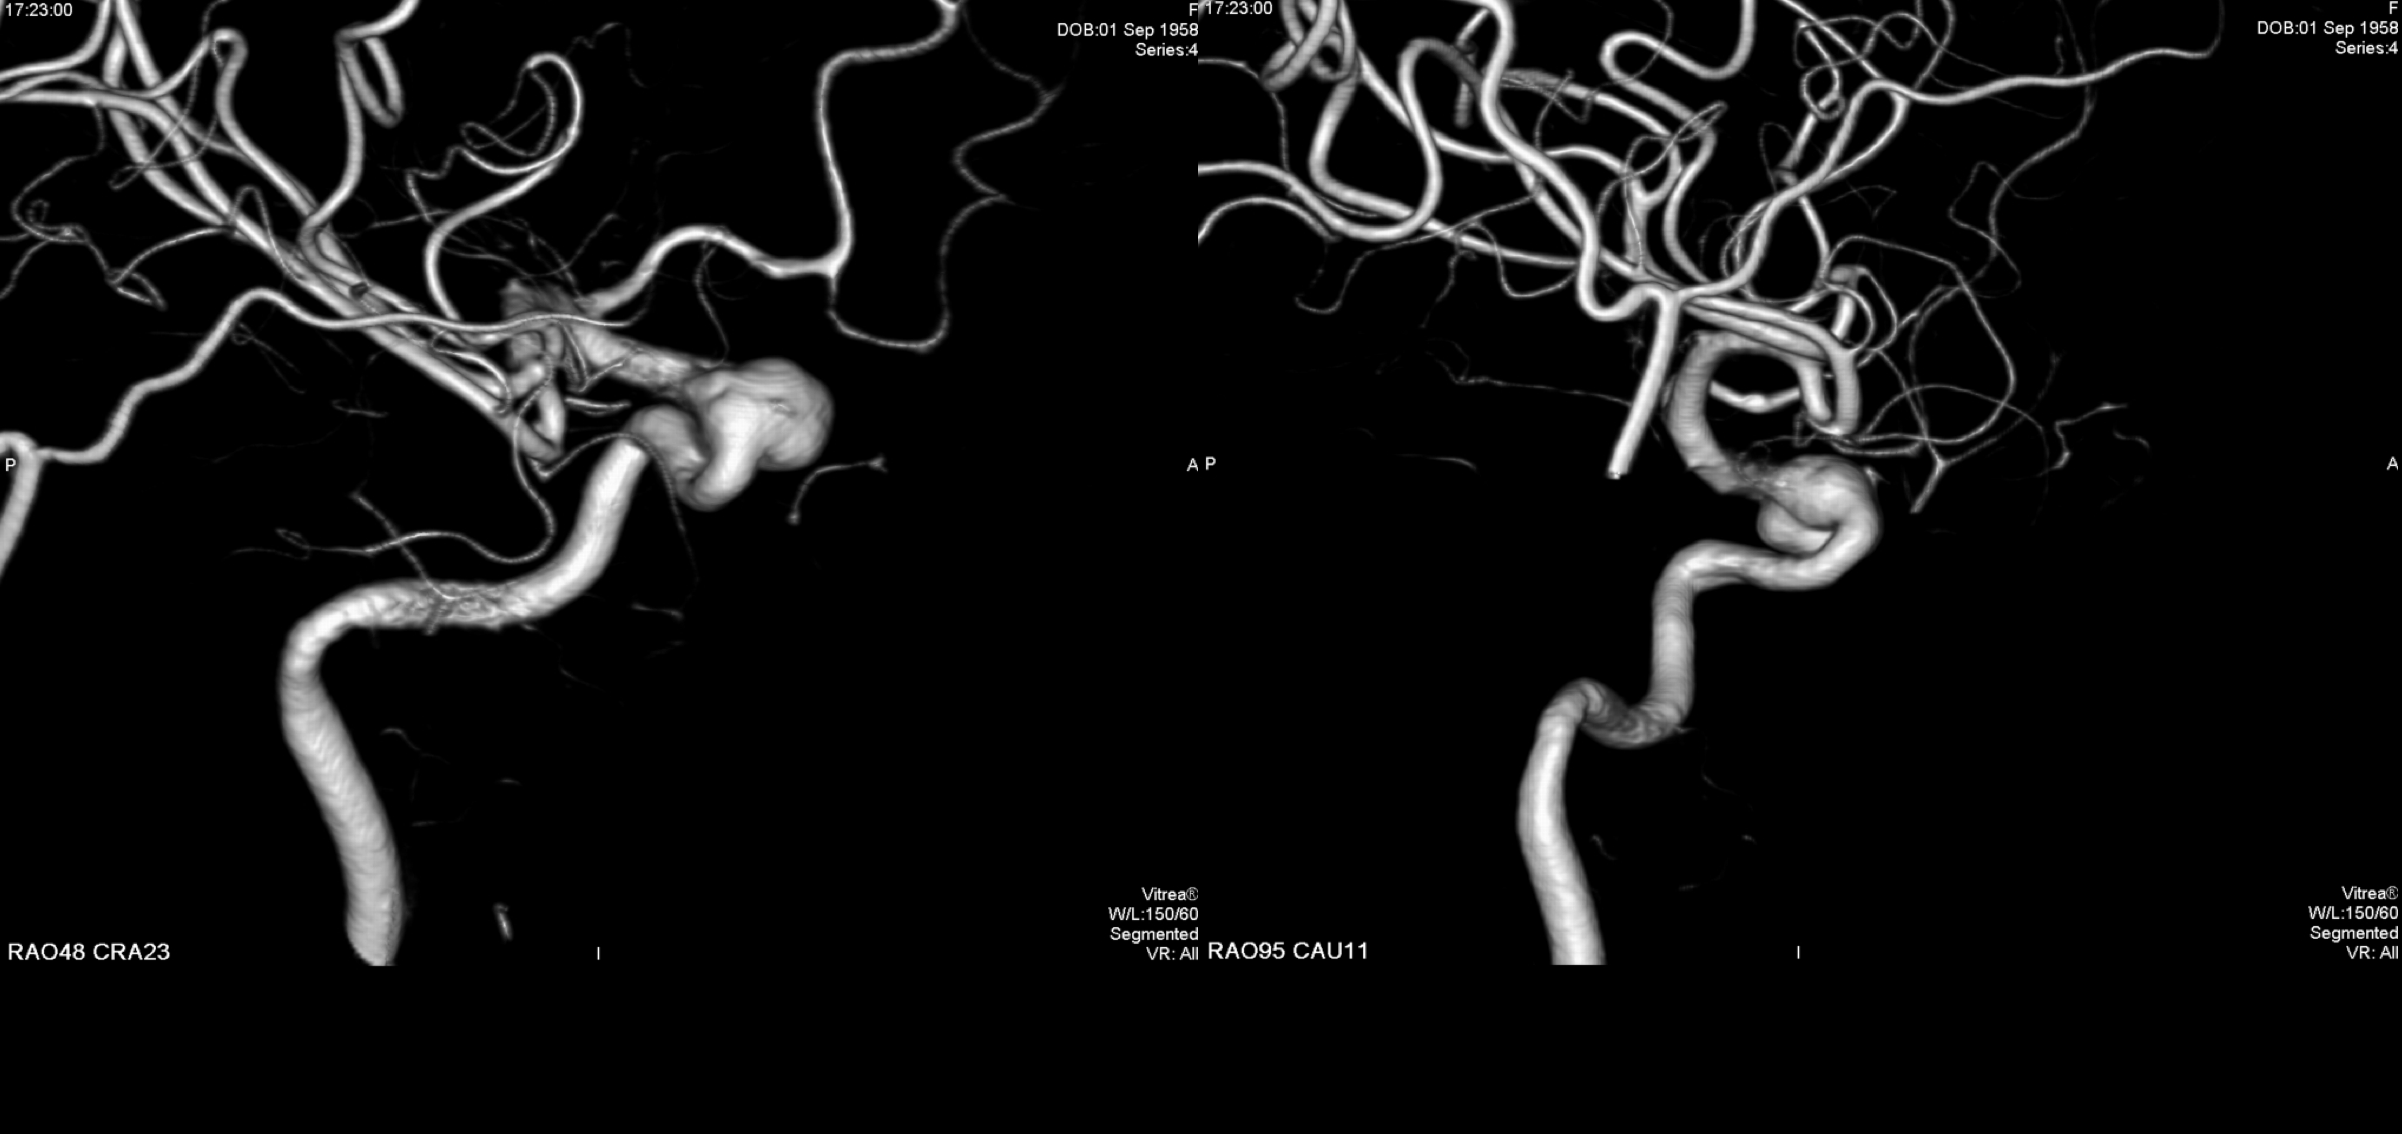

右侧颈内动脉三位造影重建:眼动脉段动脉瘤。给予支架辅助栓塞治疗。

Headway-21支架导管及Headway-17栓塞微导管到位后,根据载瘤动脉支架选择Lvis 3.5*20mm支架经支架导管输送到位!